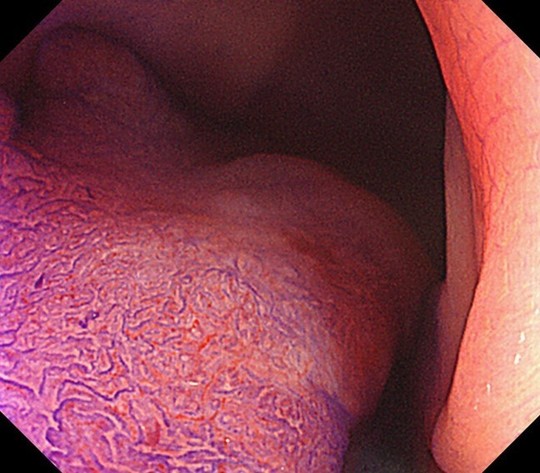

早期大腸がんのNBI拡大観察画像

表面の血管模様を確認し腫瘍の性質を判断します